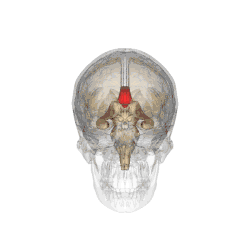

Corpus callosum from above, front part at the top of the image